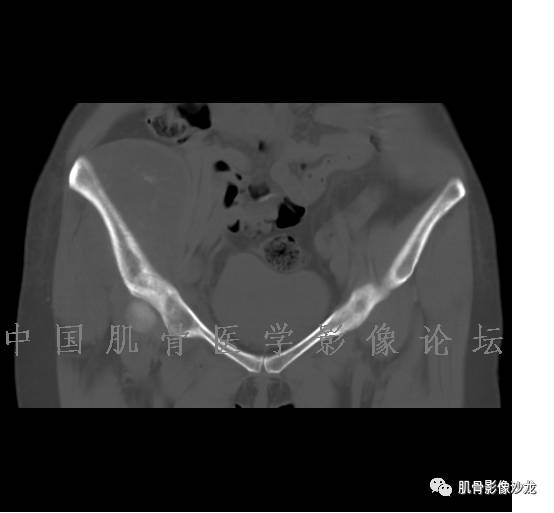

患者于2月前无明显诱因下出现腰骶部疼痛,夜间为重,逐渐加重伴左下肢麻木、疼痛,并有行走活动受限,在我院就诊,摄腰椎及骶髂部CT提示:腰椎骨质退变,腰3-4、4-5椎间盘膨出,骶髂关节炎。自用非甾体抗炎药无好转,再次来院就诊,门诊拟“骶髂关节炎”收住我科。病程无间歇性跛行,大小便正常。

辅助检查:腰椎及骶髂部CT提示:腰椎骨质退变,腰3-4、4-5椎间盘膨出,骶髂关节炎。

雪舞 :第二例,位于骶骨,有骨质破坏并有软组织肿块,软组织肿块边界清

雪舞: 第二例我们能够看到破坏与软组织肿块不成比例,软组织肿块大,破坏小

雪舞 :第二例挺难的,骨质破坏是溶骨性的,局部皮质中断,软组织肿块外缘光滑

雪舞 : 软骨肉瘤的发病率居原发性恶性骨肿瘤的第三位,其特点是肿瘤内具有软骨基质

雪舞:弓形钙化,钙化比例少于面积的1/3,钙化边缘模糊

雪舞 : 都是软骨肉瘤鉴别于内生软骨瘤有意义的区别点